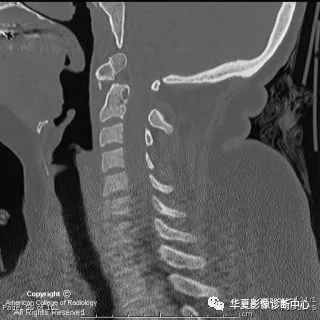

【影像图片】CT MPR图像

The sagittal CT neck image in Figure 2 shows signs of C1 anterior arch hypertrophy (green arrow). There is no paravertebral swelling. The posterior atlanto-dens interval (PADI) also known as the space available for cord (SAC) is 12mm (less than 13mm has a poor prognosis).

矢状位的CT显示颈1椎体前弓肥大(绿箭),无明显椎旁肿胀。后方寰齿间距(又称脊髓可用空间)约12mm(小于13mm预后不良)